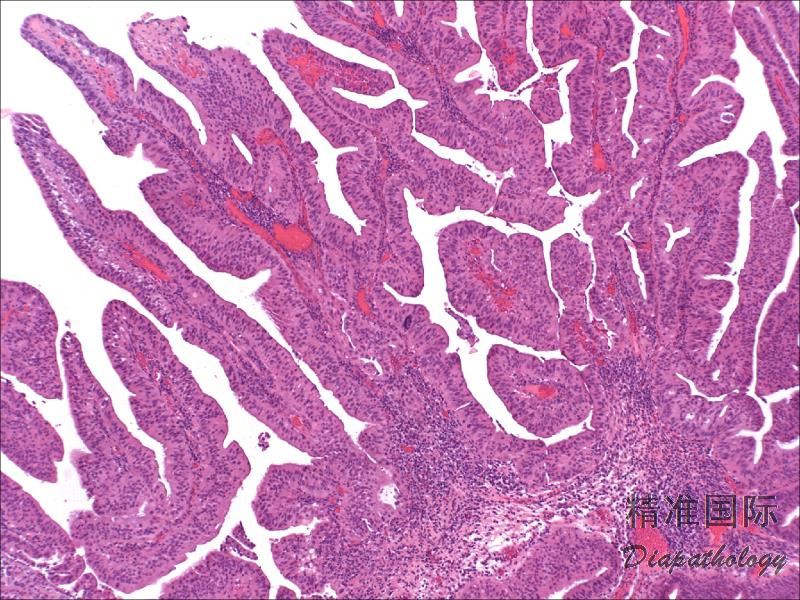

- 镜下呈具有纤维血管轴心的乳头状结构,或尖锐或钝性指状突起,被覆肠型上皮;有时可表现为管状腺瘤或管状绒毛状腺瘤;

- 上皮具不同程度的异型性,多数呈低级别上皮内瘤变,也可见高级别上皮内瘤变甚至原位癌;约 35%伴随有浸润性腺癌;

- 肿瘤周围尿路黏膜常见肠型或鳞状化生以及腺性膀胱炎。